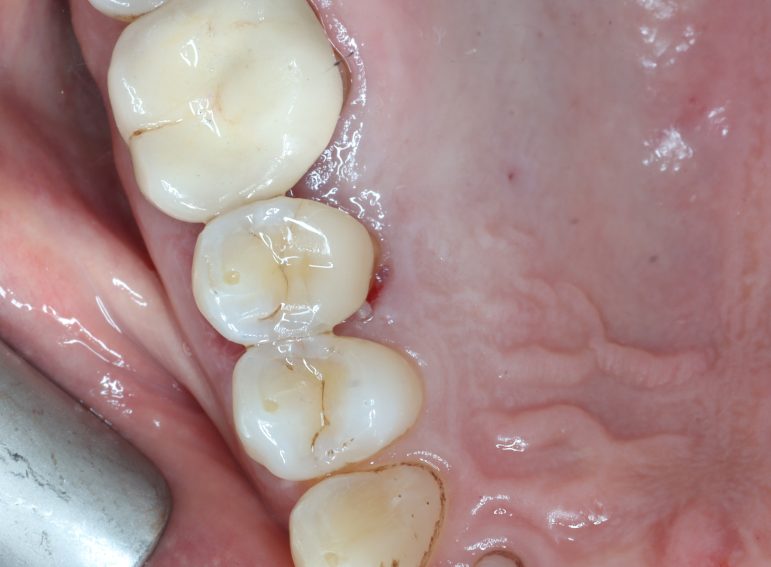

Case 6 – Periodontics

Crown lengthening Surgery on a premolar